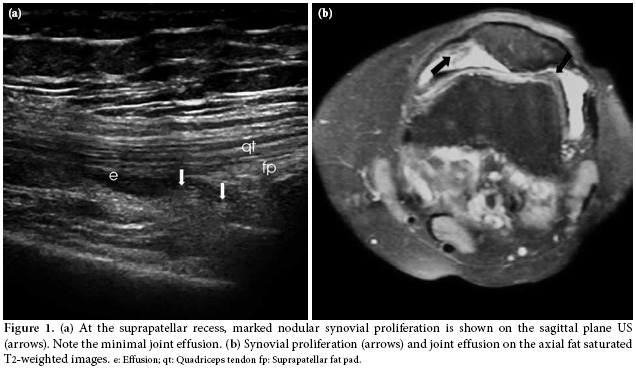

The US examination was performed first with the patient in a supine position in which the knee is flexed approximately 20-30 degrees while supported by a pillow, and the transducer was positioned longitudinally above the patella at the level of suprapatellar recess. The total synovial thickness and anteroposterior diameter of the suprapatellar bursa were measured. The synovial proliferation was considered positive when the total synovial thickness was above 3 mm, and the effusion was considered positive when it was 5 mm or higher (Figure 1a, b). During the longitudinal scan at the level of the suprapatellar recess, special attention was paid not to compress the recess. In the evaluation of the synovial proliferation, any presence of vascularization as a supporting evidence was evaluated with the color mode of the power Doppler US (Figure 2). However, because the study aimed to compare the B mode US findings and MRI findings and no contrast material was used in the MRI evaluations, spectral analyses and/or comparisons could not be made. In the same position, the patellar and quadriceps tendons were examined, and tendonitis was diagnosed if the thickness was increased and blurring and heterogeneous hypoechogenecity were differentiated.

Of the 30 knees included in the study, on 26 knees, a consensus was reached regarding joint effusion (k=0.683, p<0.001) as shown by both MRI and US The discordance was observed in four patients. In two patients, US detected minimal effusion, and the presence of physiologic fluid on MRI was reported. In the remaining two patients with discordant US and MRI findings, the MRI detected minimal effusion that was not diagnosed on the US examination.

There was also a significant concordance (k=0.595, p<0.001) on synovial proliferation, and a consensus was reached in 25 patients. Unfortunately, for the results of five patients, there was a disagreement because the MRI showed a minimal proliferation in one, which was not noticed on the US, while in the other four cases, proliferation was not seen on the MRI but diagnosed on the US. For these patients, it was speculated that the synovium might have been mistaken for the suprapatellar fat and regarded as proliferation.